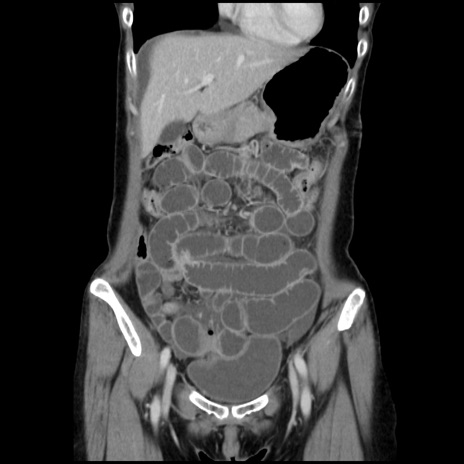

横断像

【症例】40歳代 女性

【主訴】上腹部痛、嘔気・嘔吐

【現病歴】約9時間前頃から急に上腹部痛、嘔気、嘔吐が出現。改善しないため救急要請。

【既往歴】子宮頚癌(広汎子宮全摘術、放射線療法)、腸閉塞

【身体所見】腹部:平坦、軟、腸雑音亢進、上腹部を中心に腹部全体に圧痛あり。

【データ】WBC 8400、CRP 0.03